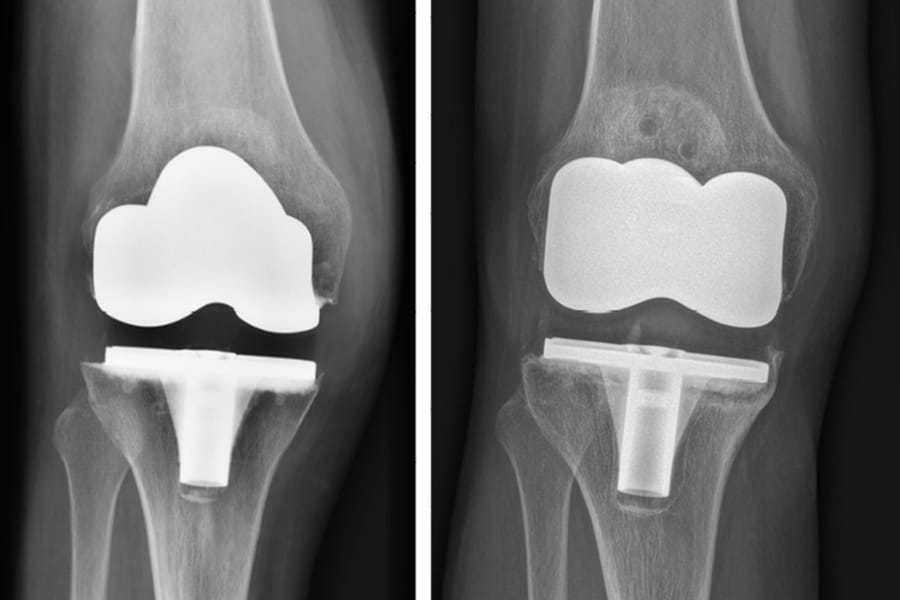

Évolution des ions métalliques après implantation d’une prothèse de genou